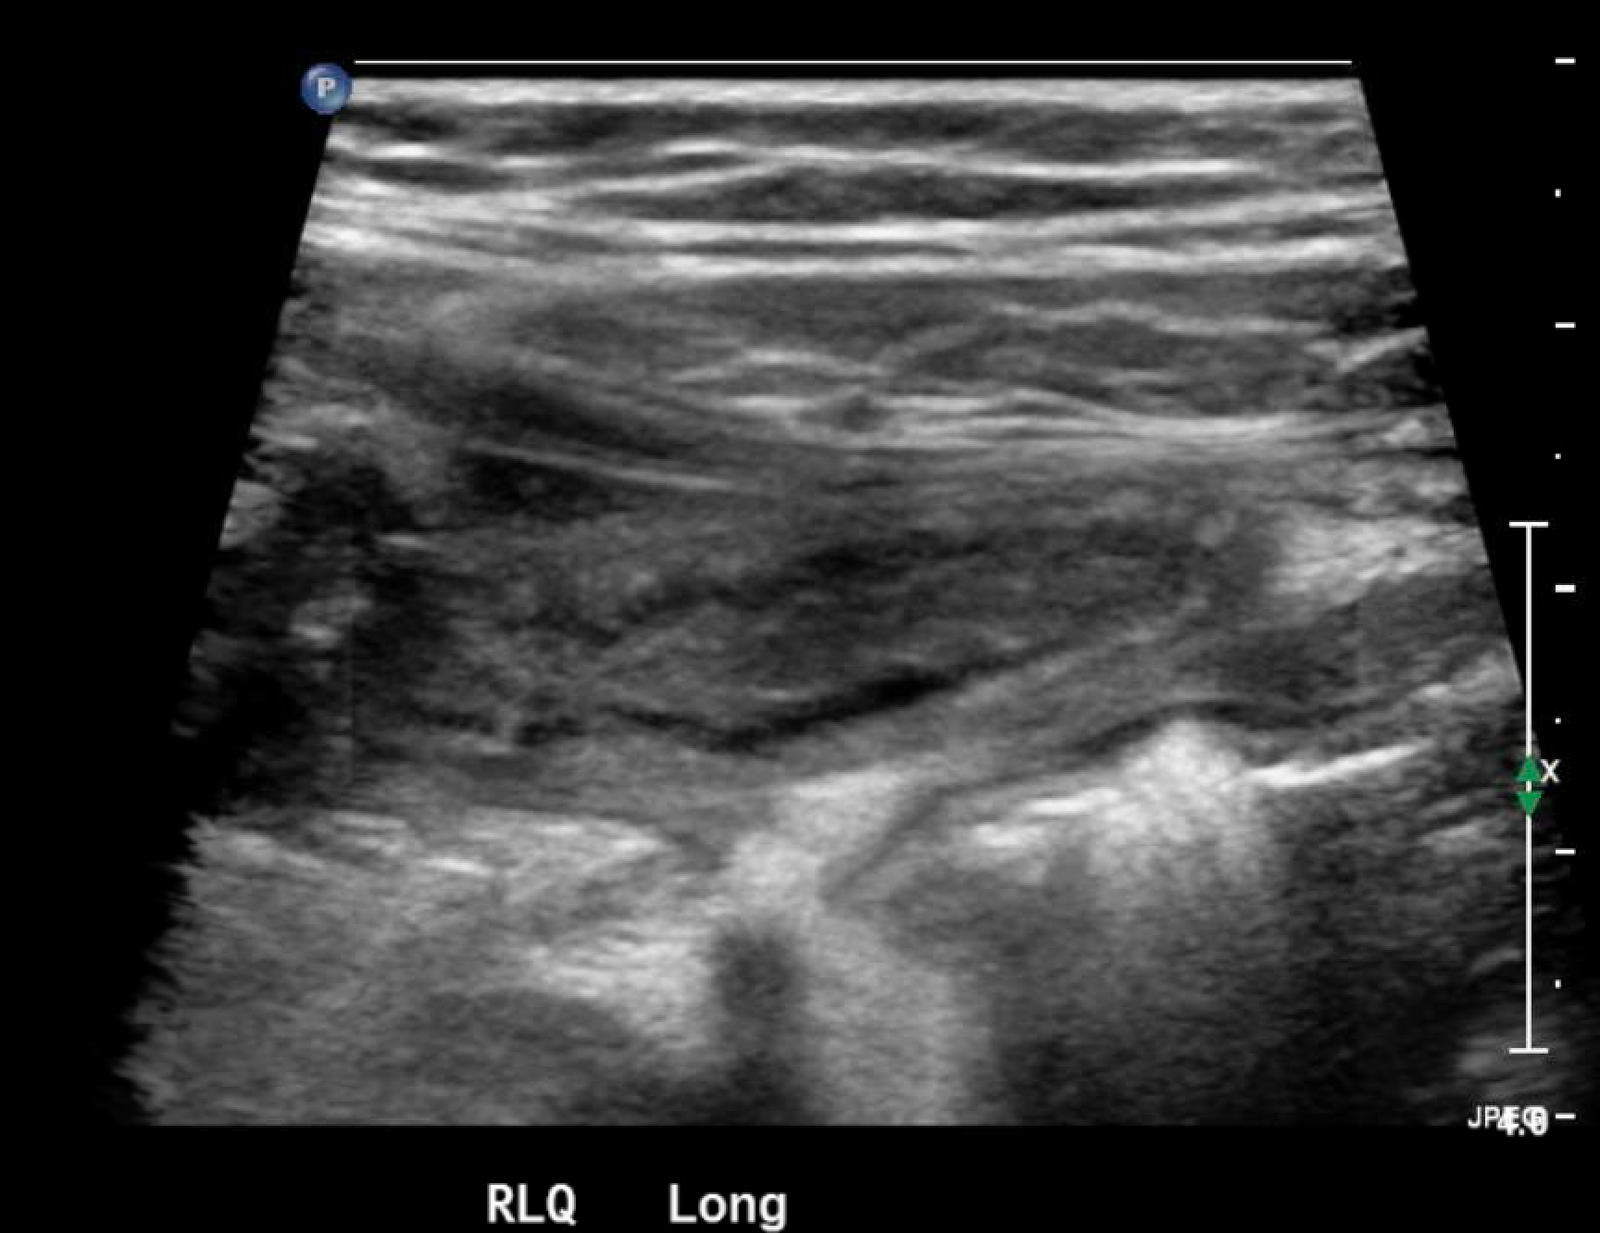

In the long axis video, the appendix appears as an enlarged, non-compressible, blind-ending tubular structure (white arrow) with distinct appendiceal wall layers and lack of peristalsis. In the short axis video, the appendix appears as a target sign (yellow arrow) between the abdominal and psoas muscles. The maximal outer diameter (MOD) measures 11.8mm and the appendix wall measures 0.17mm. There is trace adjacent free fluid and echogenic periappendiceal fat. Transverse axis video and image (red arrow) demonstrate that the appendix is not compressible. These findings are consistent with acute appendicitis.